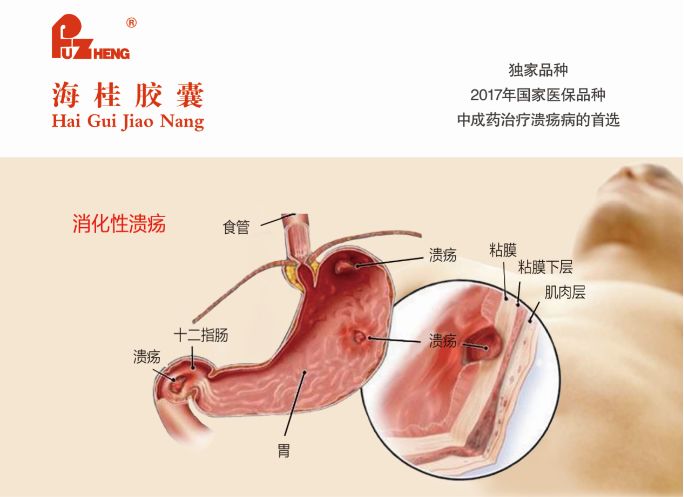

胃病患者多注意!不想演变成癌症,2件事情请远离,减少健康风险长期的胃病可能会演变为严重的胃癌。因此,胃病患者在日常生活中要特别注意一些事项,以避免疾病的恶化。下面将详细介绍两件胃病患者需... 3. 如何缓解压力 胃病患者应注重心理调节,学会释放压力,可以通过运动、听音乐、旅游、与朋友聊天等方式来放松心情。适当的体育锻炼,如...